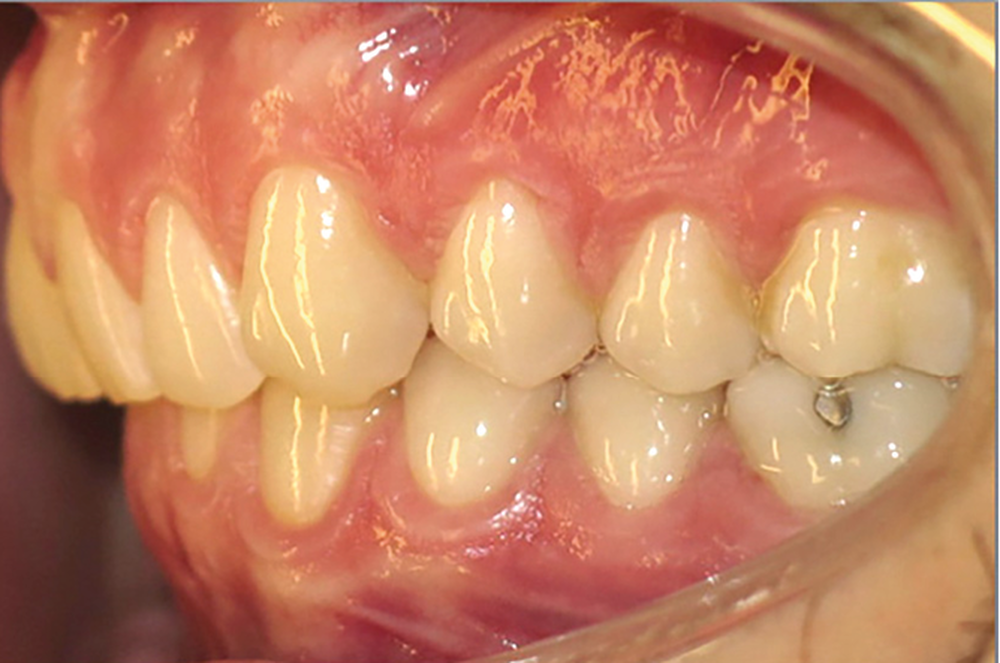

Examen endobuccal (fig. 2a-e)

L’arcade maxillaire est asymétrique, en hémi-lyre droite. Elle présente une mésio-position du secteur 1 en lien avec un encombrement antérieur estimé à 4 mm, se traduisant par une palato-position de la 12 et une rotation de la 11. On observe également des mésio-rotations des premières molaires et une palato-version incisive. L’arcade mandibulaire est ellipsoïde et présente un léger encombrement incisif (1 mm).

Concernant les relations occlusales, on observe une classe II complète subdivision droite. Le surplomb est absent et le recouvrement augmenté, estimé à 4 mm, a provoqué une usure des bords libres de 11 et 21 par attrition. Dans la dimension transversale, on constate une endoalvéolie maxillaire, ainsi qu’une concordance des médianes incisives entre elles, mais toutes deux déviées à droite par rapport au plan sagittal médian.